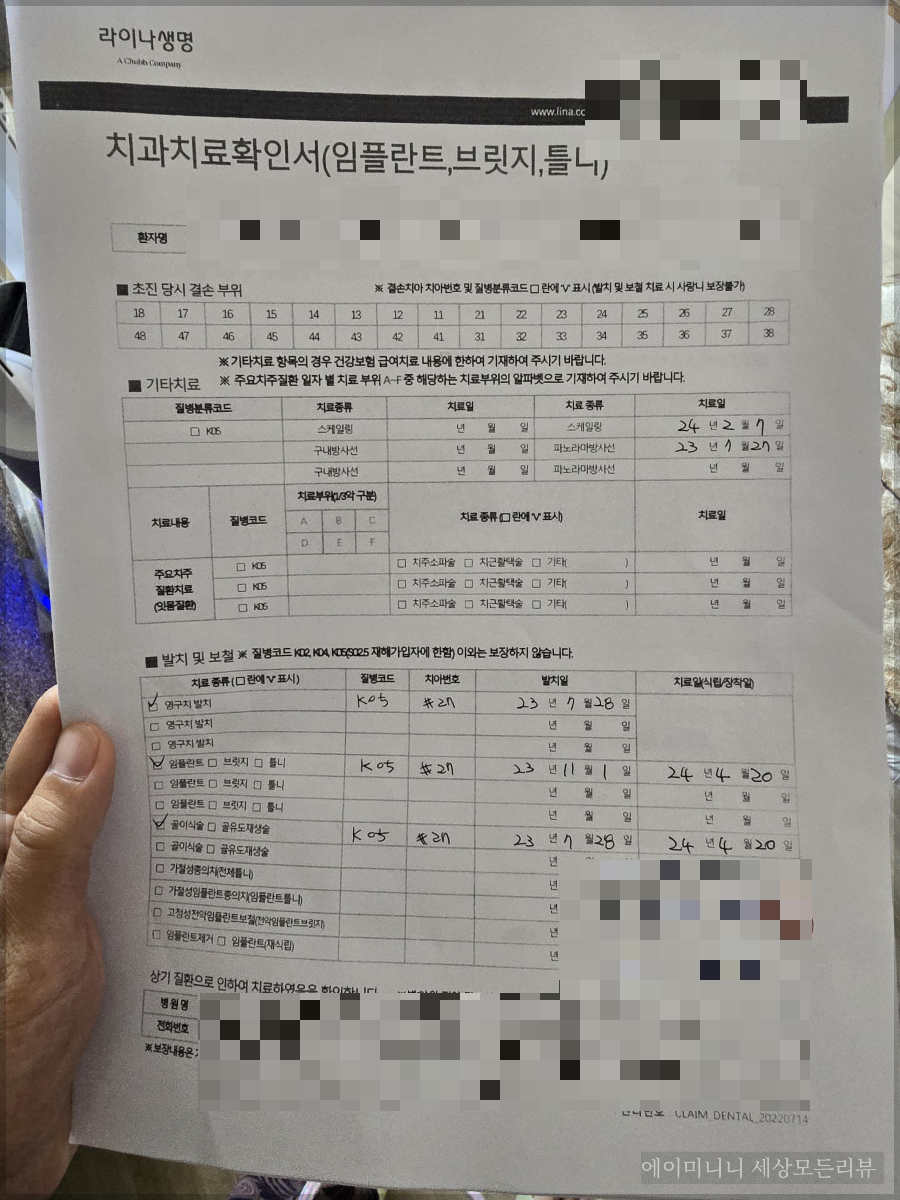

1. 라이나생명 치아보험 청구서류

우선 치과치료를 모두 받은 이후에 치과에서 작성해야할 서류가 있습니다.

일반 보험은 병원에서 진단서 등 청구서류를 떼기만 하면 되지만 치아보험은 내가 작성하는 것이 아닌 병원에서 직접 작성을 해줘야 하는 서류가 있습니다.

보통 대부분의 병원에서는 각 보험사에서 요구하는 치과 치료 서류를 가지고 있는 경우가 있지만 병원에 따라 서류가 없는 경우도 있으니 내가 들어 있는 보험사의 서류를 직접 프린트 해서 가지고 가야 할 수도 있습니다.

라이나 생명 치아보험의 경우 청구자료에 추가 서류가 있습니다.

* 치과치료 확인서

*치과진료기록 사본 (원본대조필)

*영구치 발거 전후의 X-ray 또튼 파노라마 사진 또는 이에 준하는 판독자료

필수 기재사항

*내원일(초진일)

*진단명, 한국표준질병분류번호

*영구치 치식(치아번호) 발거진단일 및 발거일

*발거 부위에 시행한 보철치료의 종류 및 치료일

치아를 선택하면 여러 종류의 치아치료에 대한 것이 나오지만 서류는 동일합니다.

<치과치료확인서>

이 부분은 환자가 작성하는 것이 아닌 병원에서 직접 작성하고 직인을 찍어줘야 합니다.

그래서 병원에 내가 어느 보험사에 가입되어있는지 얘기하고 서류가 병원에 비치되어있지 않다면 꼭 프린트를 해서 가지고 가셔야 합니다.

이전에 다니던 병원에는 이 치과치료확인서가 없었어서 프린트 해서 가지고 갔었고요.

지금 다니고 있는 병원은 병원에 서류를 비치해 놓고 있어서 치료를 끝내고 바로 발급받을 수 있었어요.

치과치료확인서 + 진료차트 + 엑스레이사진

이렇게 함께 다 받아오시면 또 방문하실 일이 없으실 듯 합니다.